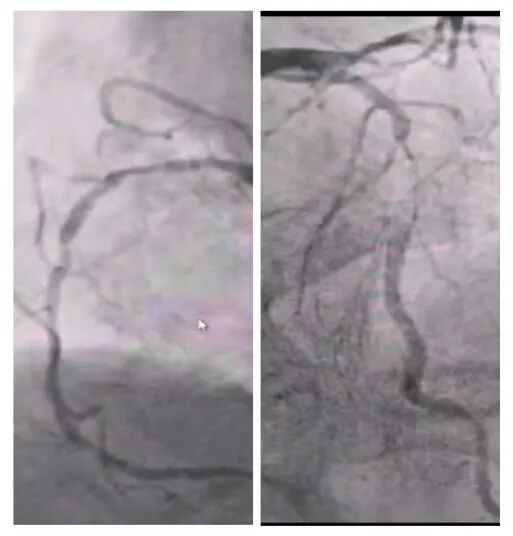

術(shù)前冠脈造影

2025年深秋的一個(gè)清晨,82歲的馬奶奶(化名)因持續(xù)胸悶氣短被家人送至醫(yī)院心內(nèi)科。心臟超聲檢查顯示,她的左心房?jī)?nèi)有一個(gè)直徑近5厘米的腫瘤,隨心跳規(guī)律擺動(dòng),如同一個(gè)隨時(shí)可能破裂的“不定時(shí)炸彈”。更危急的是,冠脈造影進(jìn)一步揭示其冠狀動(dòng)脈多支血管?chē)?yán)重狹窄,左前降支狹窄達(dá)95%,回旋支中段完全閉塞,右冠狀動(dòng)脈彌漫性病變—兩種致命性心臟疾病的疊加,讓這位高齡患者的生命岌岌可危。